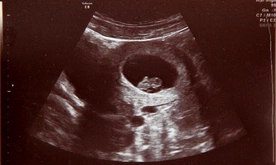

W łonie matki ratują życie Reprodukcja: Przemysław Kucharczak /Foto Gość Obraz z badania usg -widoczne jest dziecko w 7. tygodniu ciąży

Do niedawna poważne wady płodu oznaczały dramat i brak nadziei. Postęp perinatologii sprawił, że lekarze diagnozują i leczą dzieci w łonie matki - powiedział prof. Przemysław Kosiński. Ale żeby leczyć, trzeba rozpoznać. Dlatego zaleca, by USG wykonywać co najmniej trzy razy w czasie ciąży.

- Kluczem jest jednak diagnostyka prenatalna. Bo żeby leczyć, trzeba najpierw rozpoznać. USG jest bezpieczne i powinno być wykonywane co najmniej trzy razy w każdej ciąży. Czasem jedno badanie decyduje o tym, czy dziecko będzie żyło - podsumował specjalista.